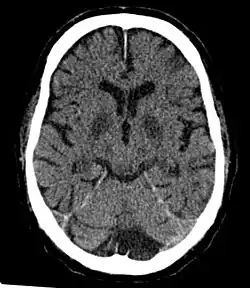

CT in a person after generalized hypoxia.

The brain requires approximately 3.3 ml of oxygen per 100 g of brain tissue per minute. Initially, the body responds to lowered blood oxygen by redirecting blood to the brain and increasing cerebral blood flow. Blood flow may increase up to twice the normal flow but no more. If the increased blood flow is sufficient to supply the brain's oxygen needs then no symptoms will result.[6]